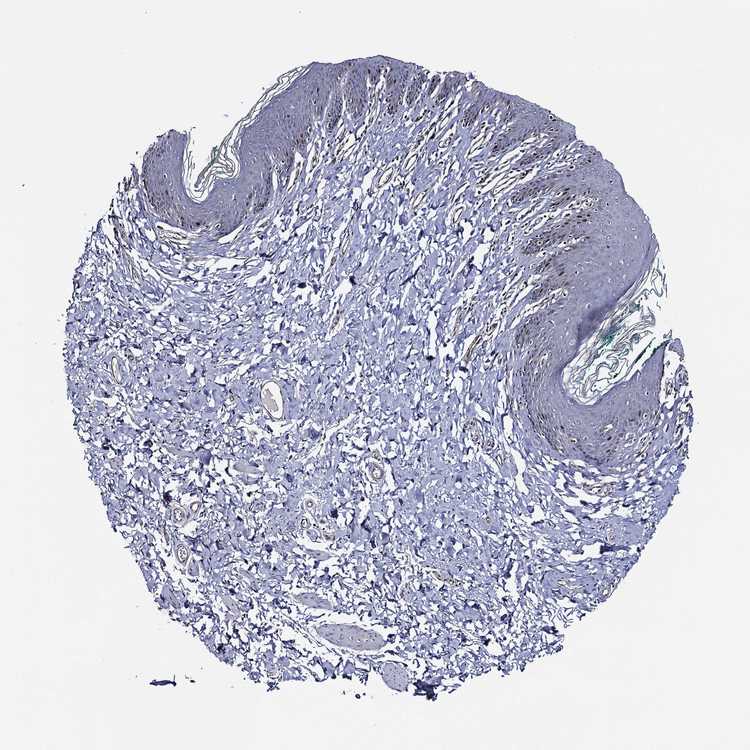

SKIN 1 - Antibody stainingi

Antibody staining in the annotated cell types in the current human tissue is reported as not detected, low, medium, or high, based on conventional immunohistochemistry profiling in selected tissues. This score is based on the combination of the staining intensity and fraction of stained cells.

Each image is clickable and will lead to virtual microscopy that enables deeper exploration of all samples and also displays staining intensity scores, fraction scores and subcellular localization as well as patient and tissue information for each sample.

Antibody HPA050214

Cells in basal layer Medium

Cells in corneal layer Not detected

Cells in granular layer Not detected

Cells in spinous layer Medium

Endothelial cells Low

Extracellular matrix Not detected

Fibrohistiocytic cells Low

Langerhans cells Not detected

Lymphocytes Low

Melanocytes Low

Vascular mural cells Not detected